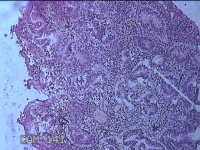

子宫腔赘生物

性别

女

年龄

33岁

临床诊断

子宫内膜息肉?子宫异常出血

一般病史

阴道流血12天。

标本名称

大体所见

灰白粉红色不规则肿物1.5x1.3x0.2cm一堆,表面糜烂。

图4